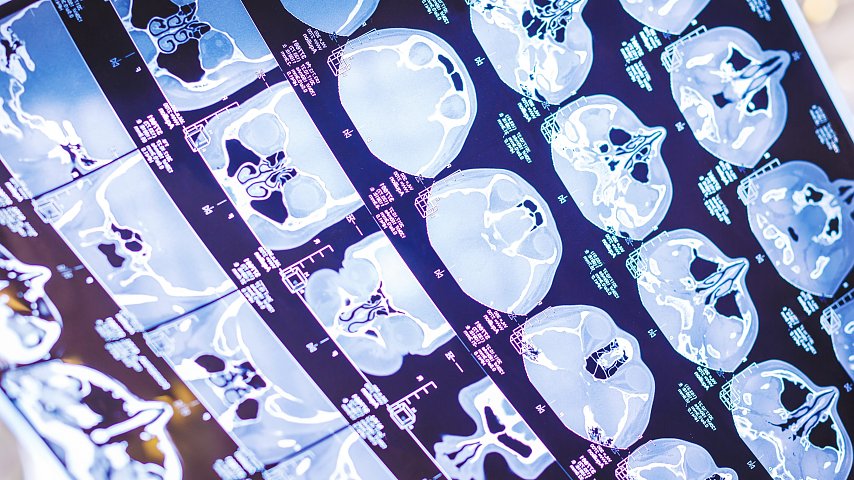

W trakcie posiedzenia wiceminister Gadomski przedstawił informację na temat zwiększenia skuteczności profilaktyki nowotworów i poprawy zgłaszalności pacjentów do programów badań przesiewowych nowotworów piersi, szyjki macicy i jelita grubego. Przyznał, że „profilaktyka onkologiczna w czasie pandemii została mocno ograniczona”. – To niebezpieczne, nie tylko z perspektywy indywidualnego pacjenta, ale również systemu ochrony zdrowia – każde opóźnienie na tym etapie skutkuje tym, że pacjenci diagnozowani są w bardziej zaawansowanym stadium choroby, a to oznacza zarówno trudniejsze, jak i bardziej kosztochłonne leczenie – wyjaśnił Gadomski, wskazując, że „jedną z grup chorych onkologicznie, na którą pandemia wpłynęła najmocniej, są pacjenci z rakiem płuc”. – Dlatego program niskodawkowej tomografii komputerowej w nowotworze płuca, który od 2019 r. realizowany jest w formie pilotażu w sześciu makroregionach, wkrótce zostanie rozszerzony na cały kraj. Zdecydowaliśmy, że nie będziemy czekać na wyniki pilotażu, bo sytuacja w tym obszarze wymaga szybkiego działania – zapowiedział Gadomski.